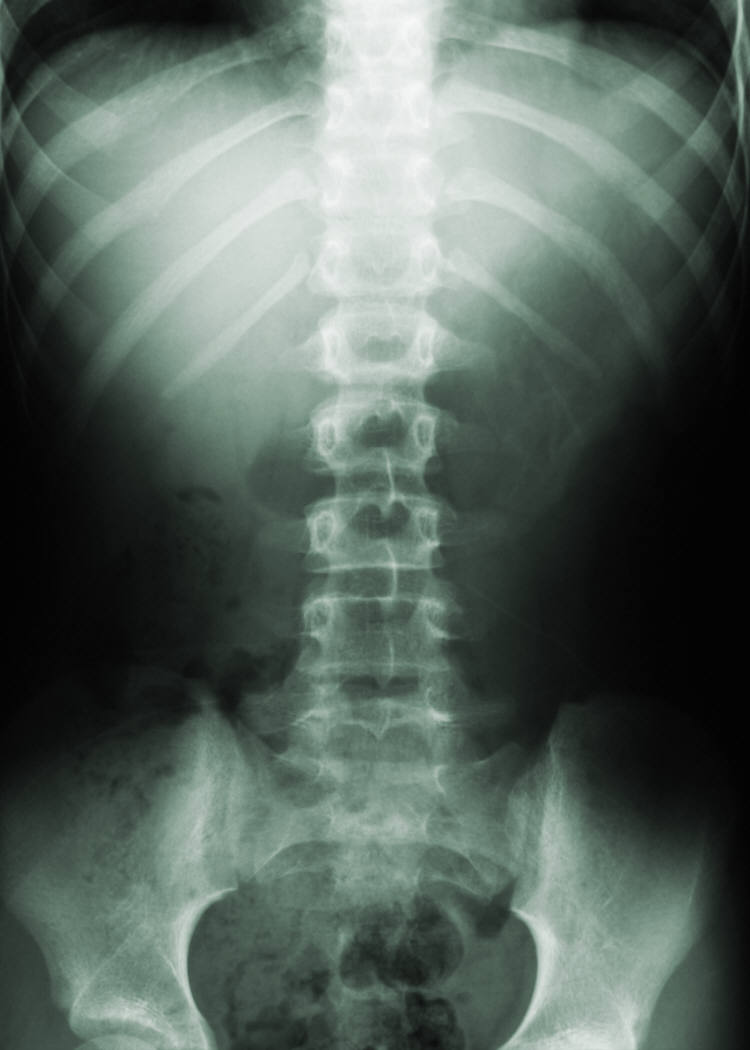

The only picture of stomach I have